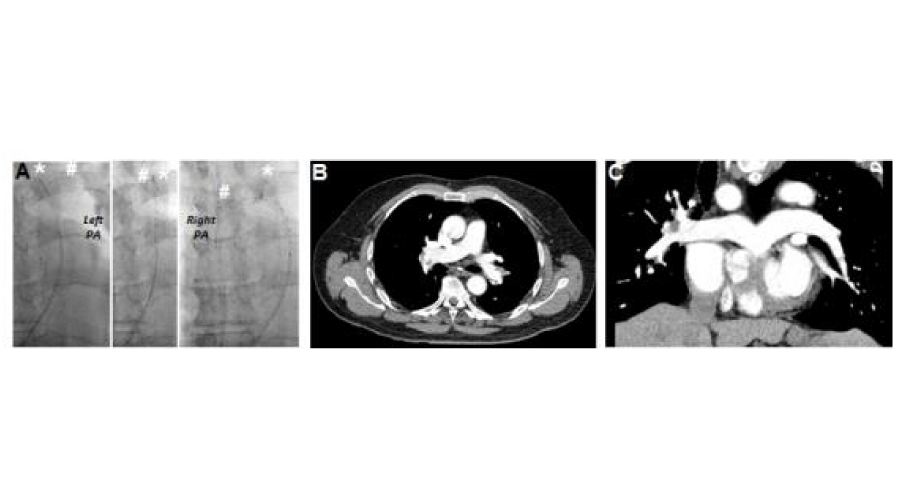

Bilateral staged USAT achieved with the use of the same thrombolysis Assisted Catheter Directed Thrombolysis N=30) is superior to management with anticoagulation alone (n=29) in the reversal of right. Assisted Catheter Directed Thrombolysis.